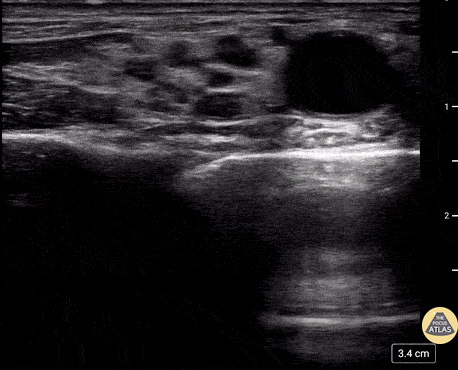

Lateral femoral cutaneous nerve block. Clip attached is one of the actual block being performed for a male patient with a large vertical laceration along the lateral aspect of the proximal thigh. Tom Jelic @tomjelic